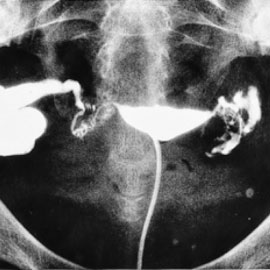

حيث تستخدم أحدث التقنيات والاستقصاءات السريرية والمخبرية والشعاعية المساعدة على تشخيص سبب العقم أو نقص الخصوبة، وبالتالي التمكن من المعالجة الطبية لتلك الحالات، أو تحضيرها للمعالجة الجراحية أو التنظيرية، أو إدراجها ضمن برامج الإخصاب المساعدة على الحمل.